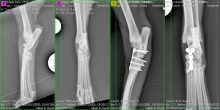

Treatment of a radius and ulna fracture in a Whippet

By Eastcott Referrals Orthopaedic Surgeon Fabio Frazzica A 1-year-old female Whippet presented with a distal diaphyseal, simple, transverse, closed ...